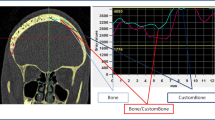

The last follow-up CT and MR images available in our database were used for analysis. Each multiplanar CT scan was performed with 1-mm slice thickness and a slide resolution of at least 512 × 512 pixels. These images were used to assess the bony anchorage of the prosthesis since CT is by far the superior imaging technique for bone structures. For the evaluation of osteointegration, we used the definition suggested by Staffa et al. [21]. They define osteointegration as a structural and functional connection between autologous bone and the prosthesis and state that this condition is achieved when the radiolucent line between the living bone and the implant is vanished on CT. A neurosurgeon, a neurosurgical resident with 2 years of experience in the field of radiology and a neuroradiologist independently carried out qualitative evaluation of the CT images. The patients were subsequently divided into six different groups based on the estimated percentage of the contour at which osteointegration has occurred (I, 0% = no osteointegration noticeable; II, 1–10%; III, 11–25%; IV, 26–50%; V, 51–75%; VI, 76–100%). Additional software was used to quantify the percentage of the contour of the prosthesis at which bony anchorage has occurred. This calculation was done by a new analysing method recently developed by the collaboration of our neurosurgical department and the software engineers of Materialise (Leuven, Belgium). The applied technique was based on the measurement of the Hounsfield units in every voxel at the bone-prosthesis interface and the application of two different segmentation filters of 400 and 700 HU by using MIMICS software (Mimics Innovation Suite, Materialise, Leuven, Belgium). The average HU density of human bone ranges from 400–700 HU (spongious bone) to 1800–2000 HU (cortical bone) [26]. The lower limit for bone density lies somewhere between 400 and 700 HU but there is no clear-cut threshold. While some authors state that voxel densities should exceed 700 HU to consider them as bone, others prefer a lower limit of 400 HU. Evidently, the selection of a proper threshold determines the results of the calculation of osseous bridging and osteointegration ratios will be lower if a more strict limit is chosen. Since there is no consensus about an exact threshold, we used both 400 and 700 HU as filters. The exact technique is described in Fig. 1a, b.

a First, the prosthesis and skull were accurately segmented from each other. On the wrapped prosthesis, a surface was created corresponding to the contact area between the plate and the bone. This was then separated into a new part and given a thickness by applying a hollow operation in both directions. b Through application of the filters, Boolean subtraction and intersection, the volume of the contact area that has a Hounsfield unit greater than 400 HU could then be calculated. This corresponds to areas of osseous bridging between the implant and the skull. In areas with a density lower than the threshold of 400 HU, we concluded that no osseous bridging has occurred at that part of the interface and that these regions consisted out of fibrous tissue and fluids. Dividing the interface volume with HU > 400 HU by the total contact area enabled us to calculate the exact percentage of the contour of the prosthesis which was structurally imbedded in the surrounding host bone